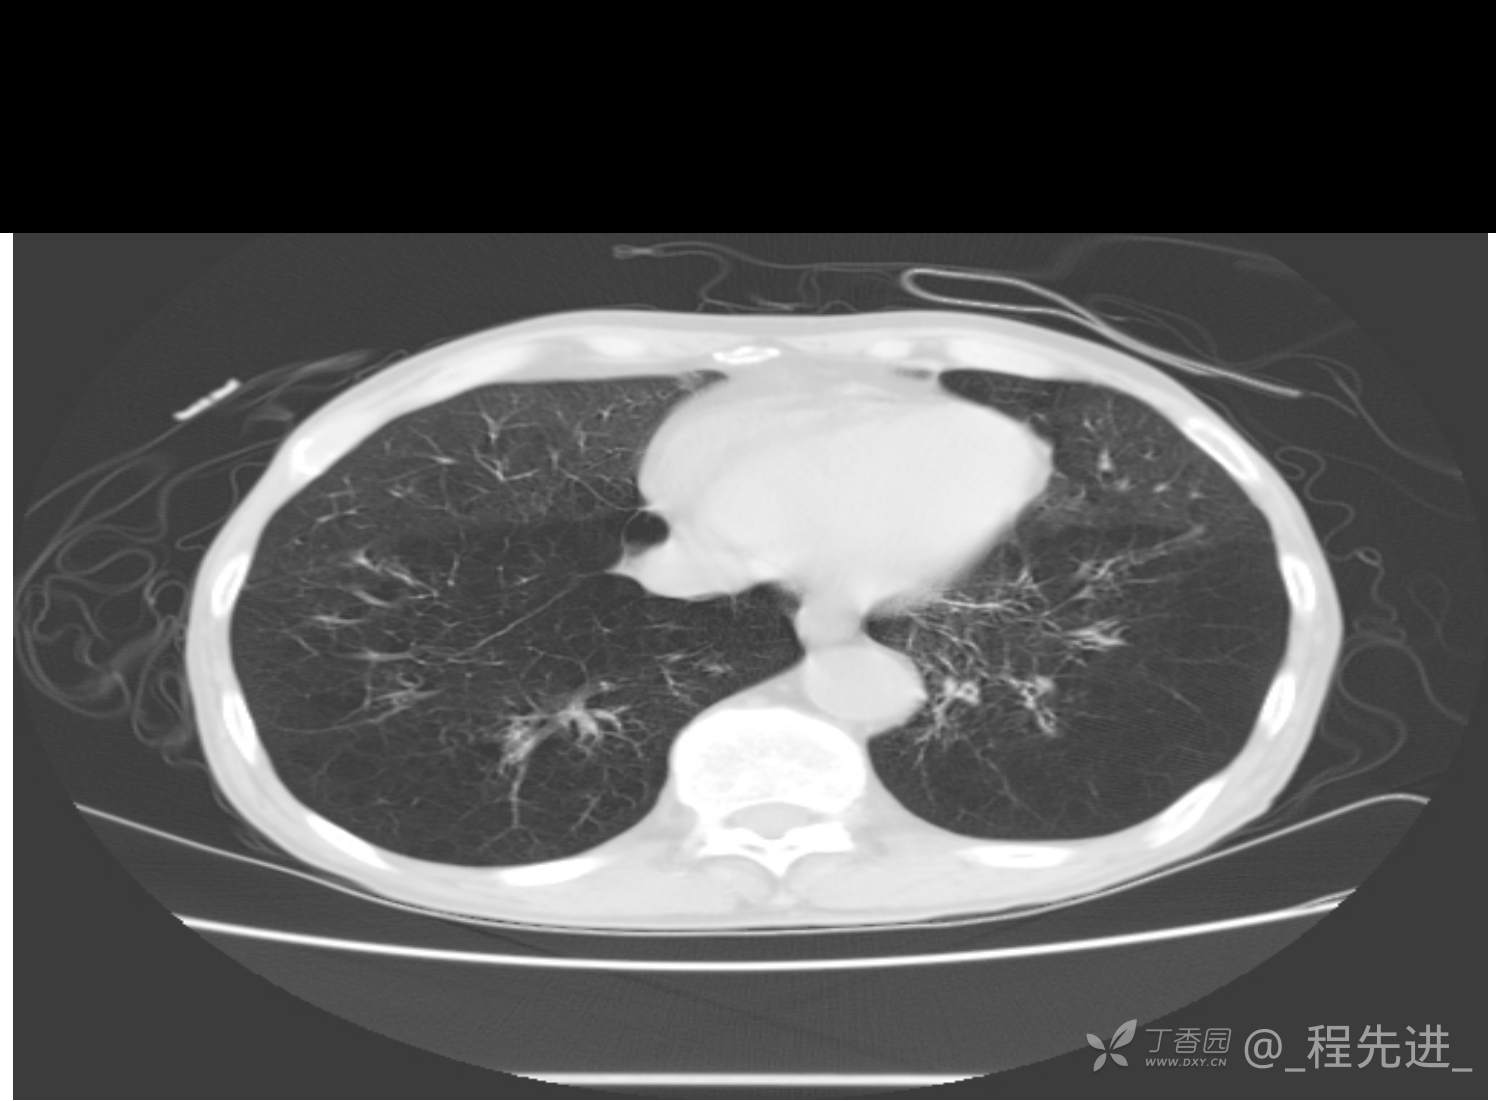

患者性别:男

患者年龄:81岁

简要病史:反复咳嗽、咳痰20余年,加重1周。两肺呼吸音低,可闻及散在干湿啰音。